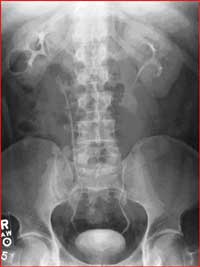

Esophagram

• Barium Swallow: evaluates the pharynx and esophagus including the swallowing mechanism. It includes conventional barium esophagram (barium swallow) and modified barium swallow (oral and pharyngeal function study).

• Upper Gastrointestinal Series: An upper GI tract exam is a study to enable the radiologist to examine the anatomy and function of the pharynx, esophagus, stomach and the duodenum. The procedure is performed using xray in motion (fluoroscopy) after the intake of oral barium contrast. Your physician may order an upper GI exam to check for: Ulcers, tumors, inflammation, hiatal hernias, gastroesophgeal reflux disease (GERD), cause of obstruction which can lead to unexplained vomiting or bleeding etiology.